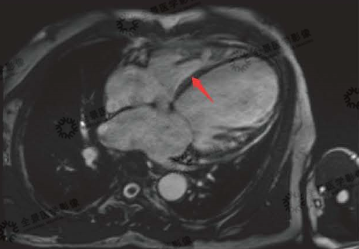

▲黑血序列:

白色箭头:正常心肌

红色箭头:水肿心肌